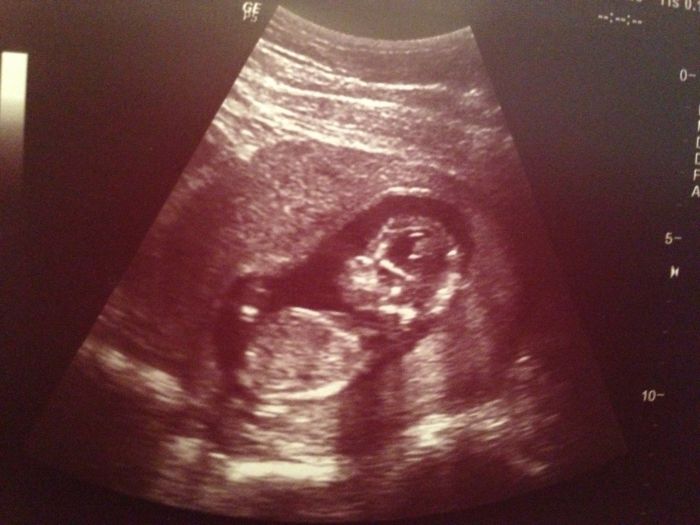

Ahoj holky tak se zas po nejake dobe ozvu ;) dnes sem byla na kontrole a vse v poradku, mimco roste jak ma, byla tam dnes misto meho doktora nejaka pani doktorka na zastup coz sem docela rada protoze psn doktor je fajn ale obcas z nej mam pocit jako ze obtezuji takze sem hned vyuzila a optala se na pohlavi ;) nooo jenze mimco nechtelo moc spolupracovat sedelo si v tureckem sedu s patickou mezi nohama a kdyz uz se konecne ukazalo tak pani doktorka rikala ze s jistotou to jeste zjistit nedokaze ale ze by se vic priklanela k holcicce coz by bylo uzasny ;) ale tak uvidime na dalsi kontrolu jdu za 4 tydny, 28.8 tak tam uz to snad bude jistejsi.Jinak k tem rekonstrukcim mi se hodlame tak do mesice stehovat uplne tak sem zvedava jak to zvladneme ;) jinak drzim palecky vsem kdo jde na kontrolu a uzivejte, posilam fotecku z dneska a taky toho rostaka co uz mame doma ;)